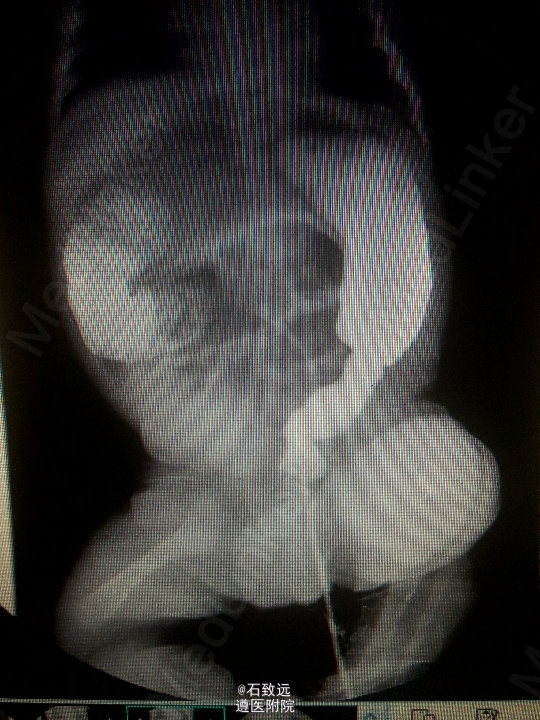

入院考虑:新生儿便血原因待查:新生儿自然出血症? 处理:予禁食水,补液,止血治疗。20h后患儿哭闹,出现腹胀,腹壁发红发亮,叩腹呈鼓音,肠鸣音弱。腹平片示:腹胀气,肠梗阻? 予胃肠减压后体温恢复正常,腹胀明显改善。入院后第15天给予开奶,患儿再次出现腹胀,禁食灌肠后腹胀缓解。行下消化道造影提示:先天性巨结肠。遂转外科行手术治疗,行“巨结肠根治术”。术后继续予补液、抗炎、抗感染、禁食水等对症处理,病情逐渐稳定。现患儿治愈出院。 出院诊断为:新生儿先天性巨结肠合并坏死性小肠结肠炎。